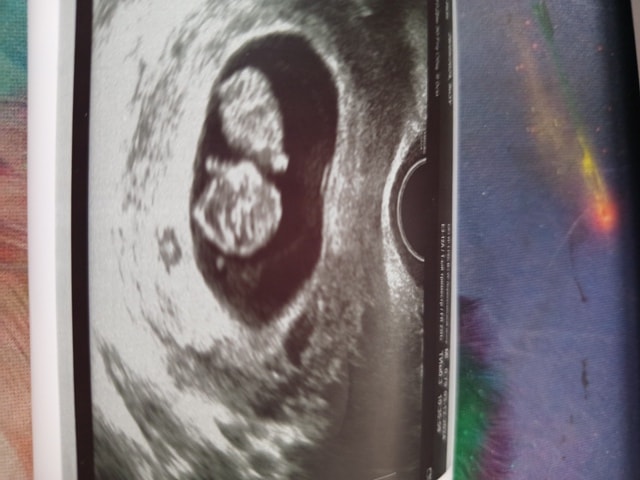

ПЯ отстаёт по сроку на 6 дней. ПЯ 25 мм (срок 7,4). Эмбрион ктр 21 мм, срок по УЗИ 8,5 недель. Врач сказала, что это нормально, такое бывает. А я вот переживаю, не задавит ли ПЯ эмбрион?

По фото ПЯ как будто сплющено.

А с виду и не скажешь что пя маленькое. Малыш свободно плавает... У меня примерно также выглядела в 8 недель

Джеллибин, ну по размером примерно одинаково. Небольшая разница. Надеюсь, что неправильно измерили, потому что по 3д снимку там много места. Ну посмотрим, записалась на вторник на УЗИ ещё.